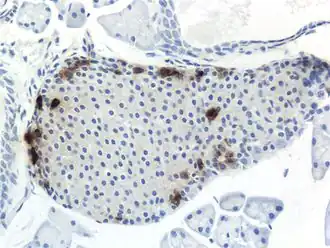

![]() Панкреатический островок мыши, ПП-клетки выделены. | |

ППома — опухоль из ПП-клеток (F-клеток) островков поджелудочной железы, секретирующая панкреатический полипептид (ПП).